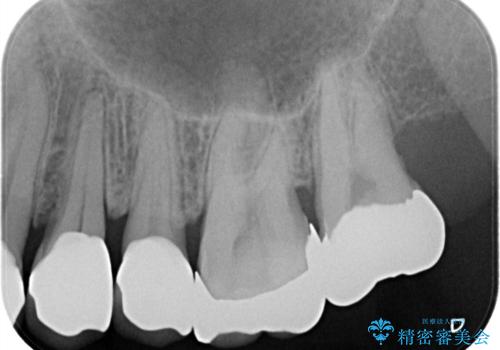

縁下カリエス オールセラミッククラウン

- 以前他院で修復した金属の詰め物の下が虫歯になっており、歯周外科を含めた歯冠修復を行っております。

歯肉縁下の虫歯は精度高い治療を行う場合、歯周外科を提案させていただくことがあります。